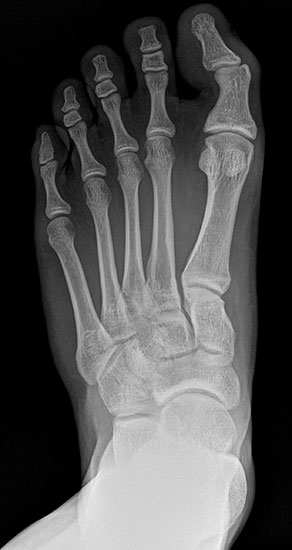

Standard ist die belastete Röntgenaufnahme des Fußes dorso-plantar und seitlich. Günstig ist eine Röhrenkippung von 10°-20°, um die Gelenke der Lisfranc-Linie einsehen zu können.

Ergänzend kann eine Schrägaufnahme hilfreich sein. Bei Metatarsalgien oder Pathologien der Sesambeine liefert die Sprinteraufnahme zusätzliche Informationen. Bei einer Pes planovalgus Fehlstellung wird ergänzend ein Saltzman view durchgeführt.

• Hallux valgus Winkel

• Hallux valgus interphalangeus Winkel

• Intermetatarsalwinkel I zu II

• Distaler Metatarsale Gelenkwinkel (PASA)

• Form des Mittelfußknochenkopfes

• Winkel Metatarsale I Basis zum Os cuneiforme mediale

• Metatarsalindex

• Elevation/ Plantarisierung I. Strahl

• Pes metatarsus adductus

• Wachstumsfugen

• Coalitiones

• Akzessorische Knochen